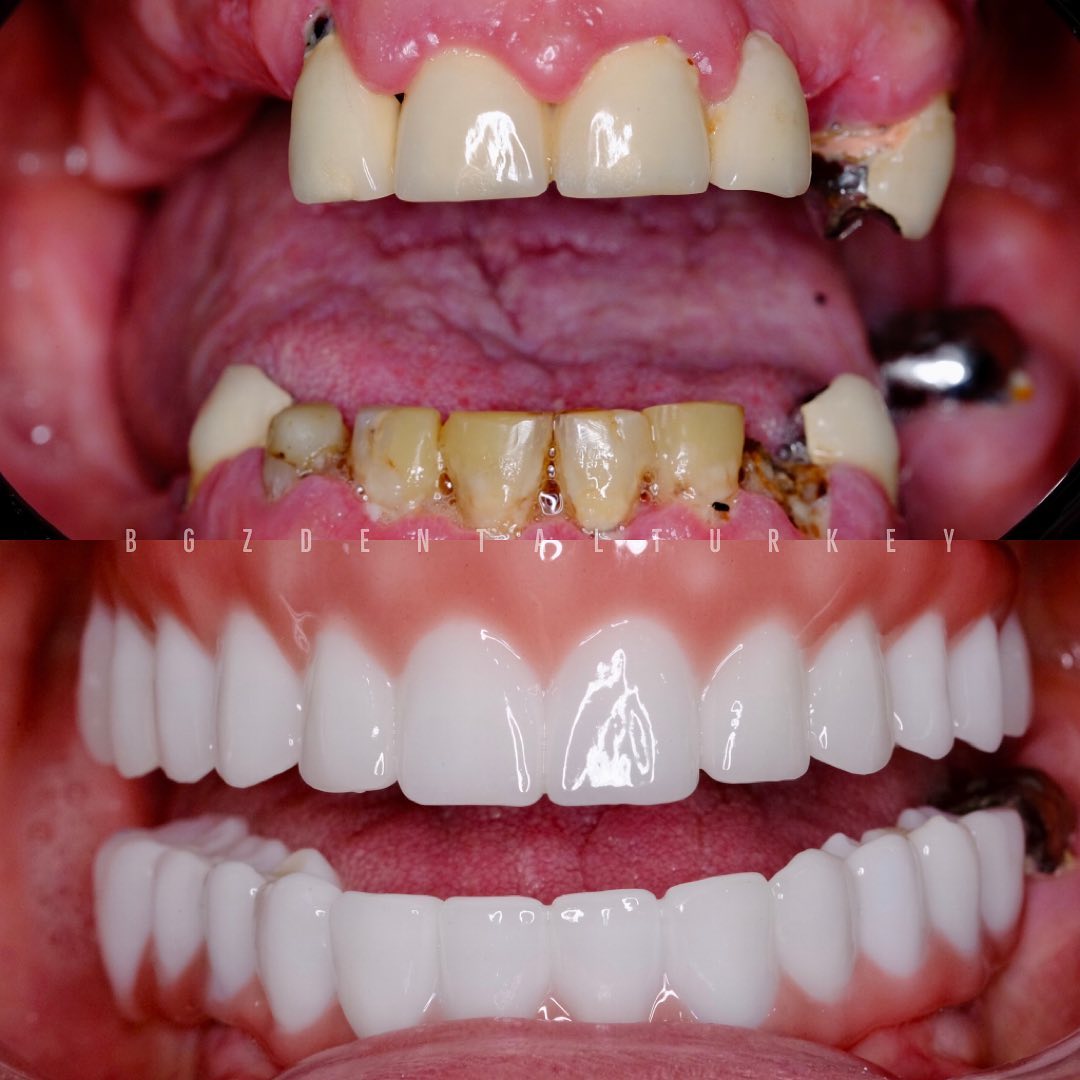

Corrección de implantes frontales fallidos para lograr una sonrisa natural y estéticamente perfecta.